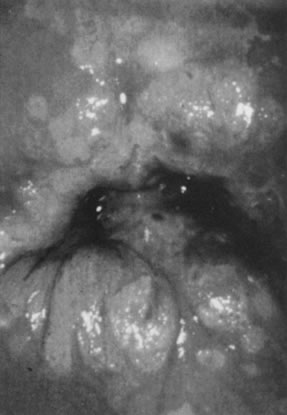

Potentially oncogenic HPV types, especially HPV-16, also may give rise to grossly visible lesions presenting as multiple, darkly pigmented, sometimes white, pale, or fleshy papules, formerly often referred to as bowenoid papulosis (Fig. 17). Histologic examination of the papules usually reveals vulvar intraepithelial neoplasia (Fig. 18).

Fig. 17. Colpophotograph of several darkly pigmented papular vulvar lesions. Biopsy showed vulvar intraepithelial neoplasia, grade 3 (see Fig. 18).

Fig. 18. intraepithelial neoplasia, grade 3. The entire thick- ness of the epithelium is replaced by atypical cells. The nuclei are enlarged but maintain some polarity. Increased cellularity and multiple mitoses are evident. (Hematoxylin-eosin, ×500.)